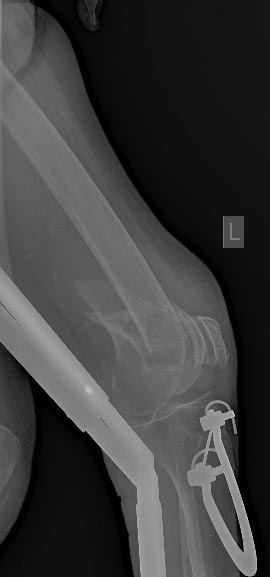

Бедро мы бы предпочли закрыто заштифтовать антеградно. Недавний пример в приложении. Насчет мыщелков - КТ надо, похоже, там импрессия есть.

ось хорошая, но гвоздь в суставе - это не проблема?

надколенник при сгибании будет болеть скорее всего